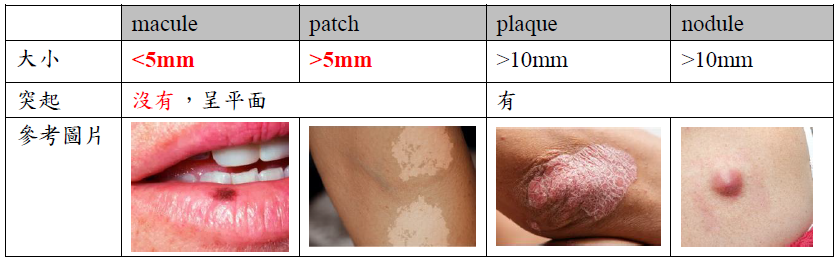

| 名稱 | 單發? | 風險/位置 | 特徵 | ||

|---|---|---|---|---|---|

| Oral melanotic Macules | 單 | 下唇朱紅區(vermilion zone, 33%), Buccal mucosa, gingiva, palate | 表面平坦、棕黑色、邊界清楚、φ<5mm  |

||

| 不須治療,但不易和 Oral melanoma 分辨 → 燒毀! | |||||

| 黑色素失禁(melanin incontinence): basal cell 可能破損 → macrophage 於 CT 吞噬 → melanophage  |

|||||

| Physiologic Pigmentation (生理性) | 多 | 黑人 | - | ||

| Chronic irritation (慢性刺激) |

|

||||

| Syndromes or Diseases Associated |

|

||||

| Drug-induced | 奎寧(chloroquine), palate | 左右沒有完全對稱  |

|||

| melanin堆積,確診直接 Bleaching | |||||